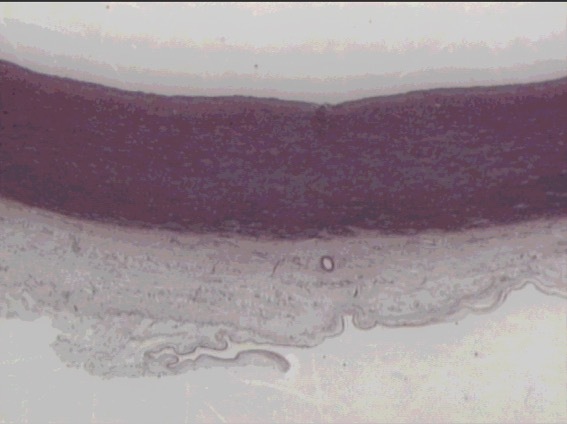

lymph node

cotex

pericortex

medulla

outer cortex lymph node (B-cells)

paratrabecular sinus

subcapsular sinus

(lymphatic fluid)

trabeculae

CT capsule

cortex

primary nodule

secondary nodule

subcapsular & paratrabecular sinus